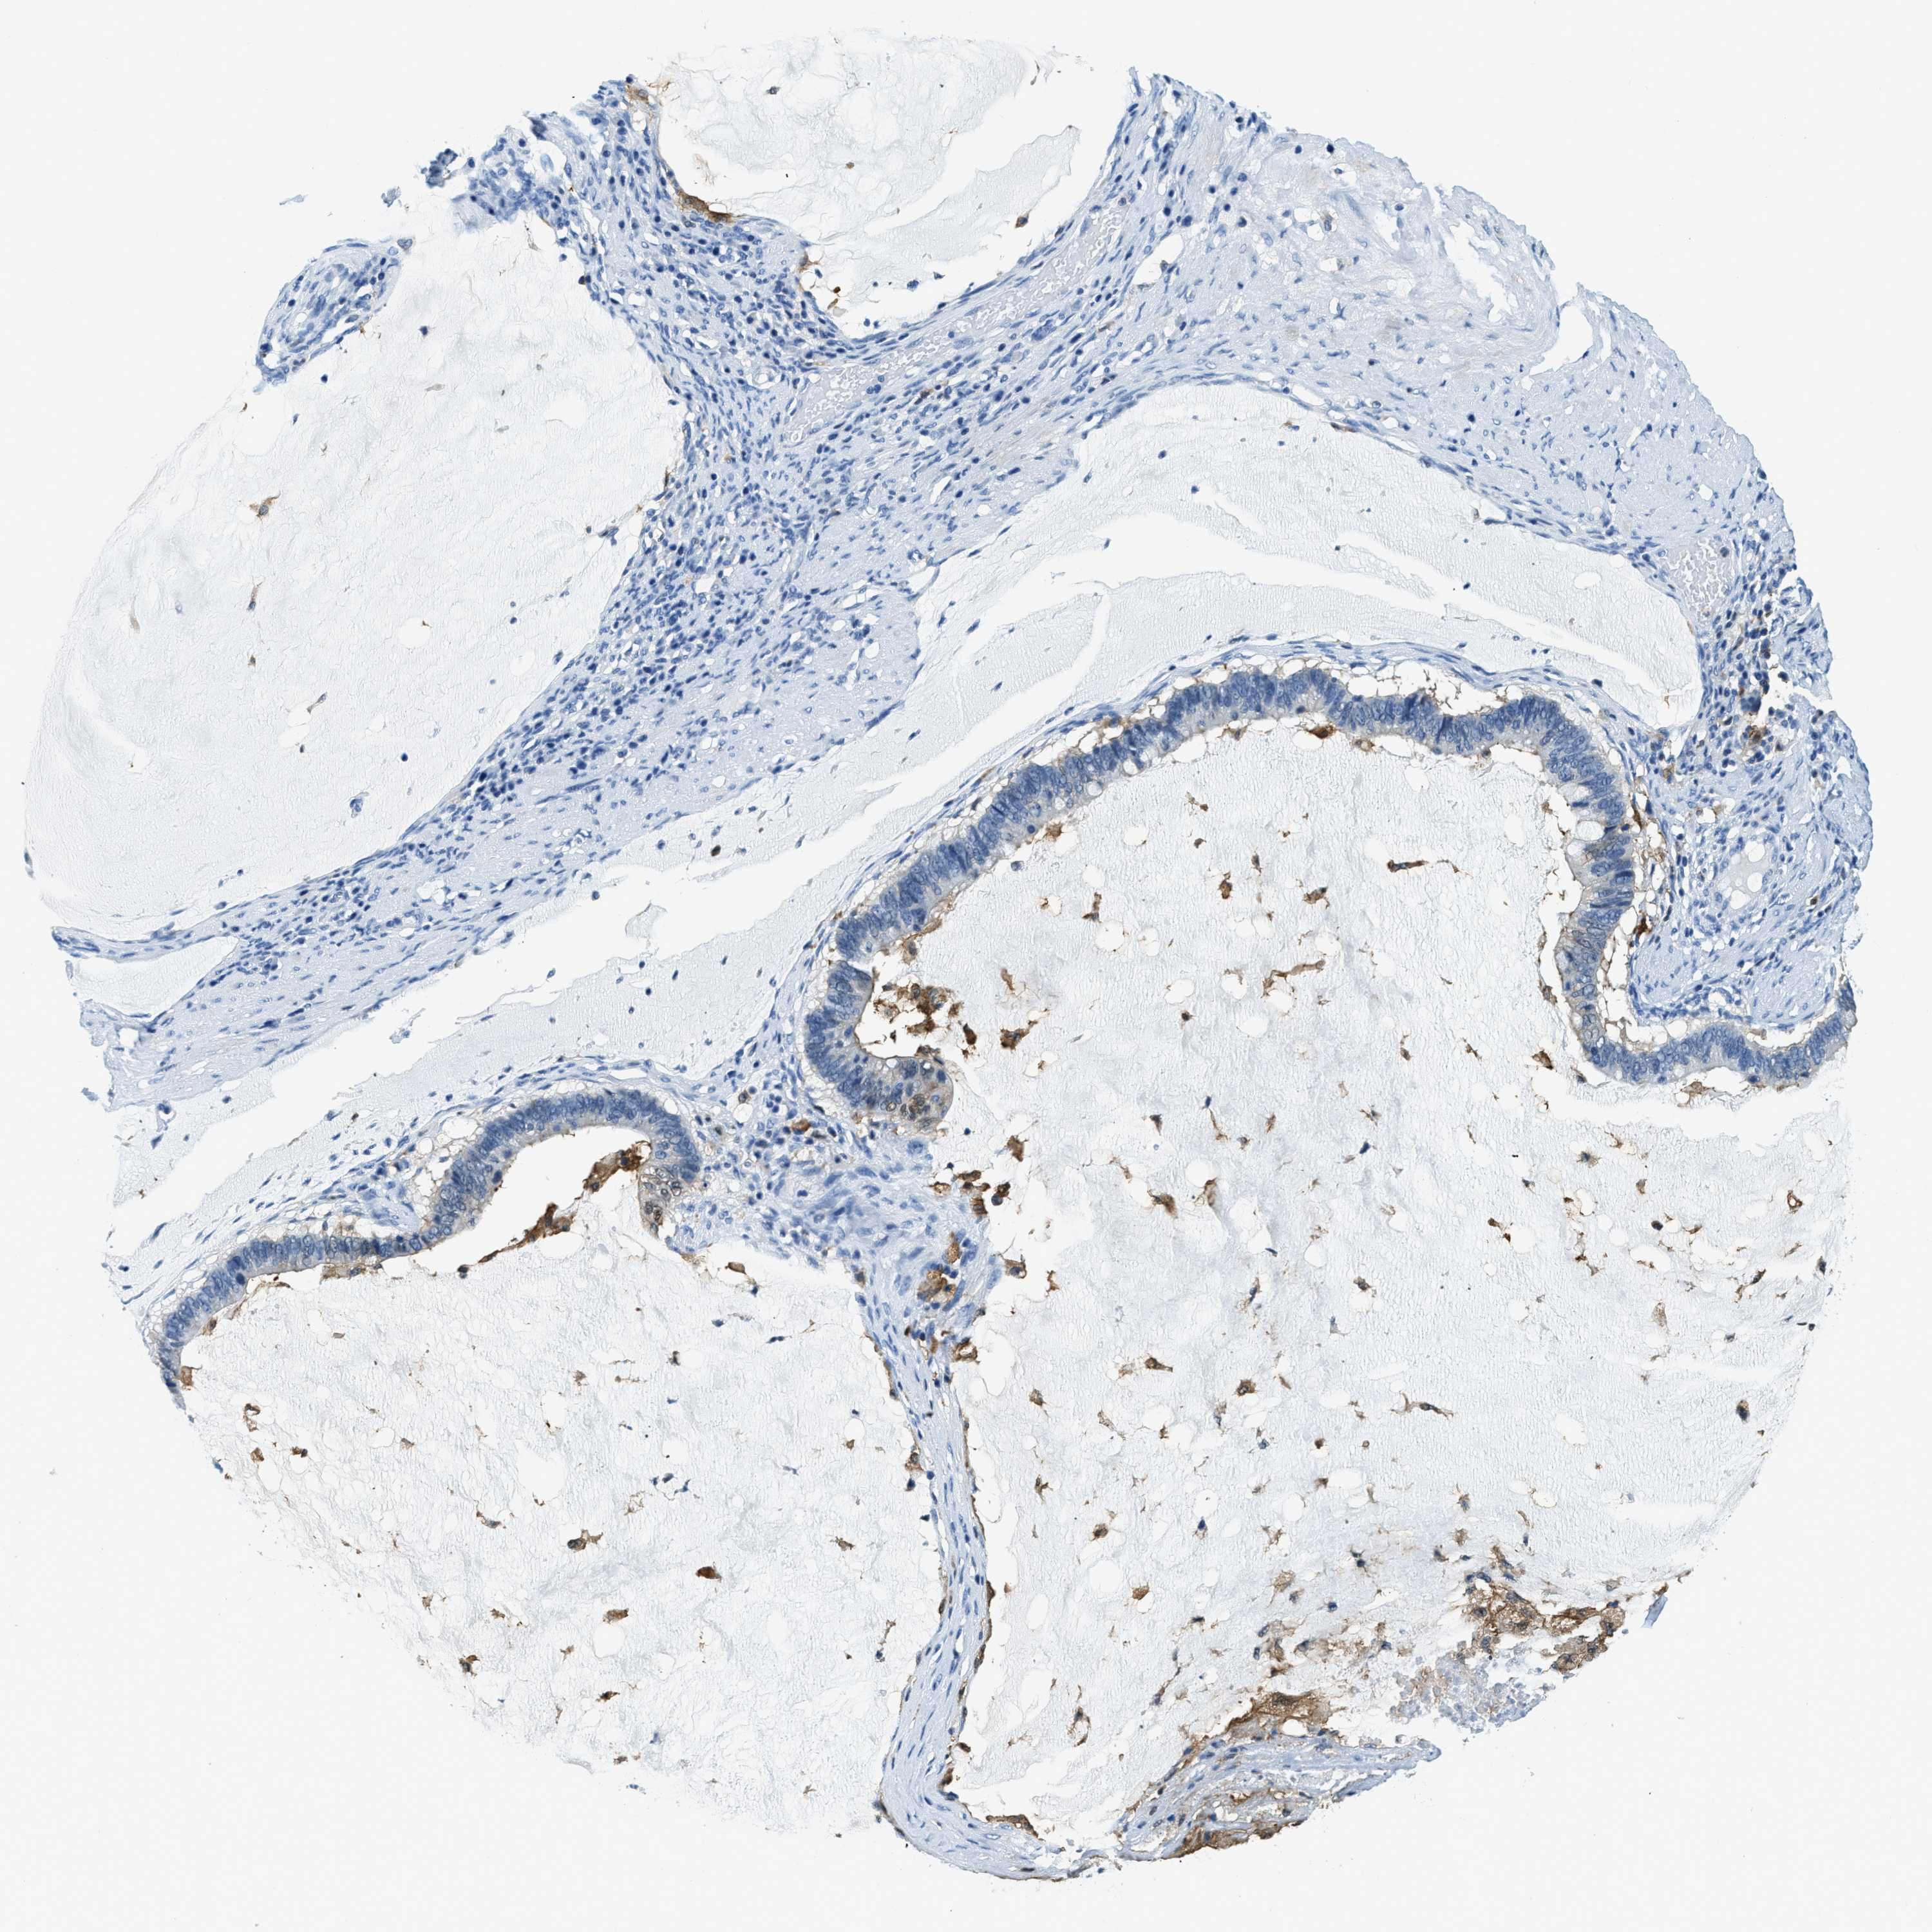

OVARIAN CANCER - Protein expressioni

A mouse-over function shows sample information and annotation data. Click on an image to view it in a full screen mode. Samples can be filtered based on level of antibody staining by selecting one or several of the following categories: high, medium, low and not detected. The assay and annotation is described here.

Note that samples used for immunohistochemistry by the Human Protein Atlas do not correspond to samples in the TCGA dataset.

Antibody stainingi

Antibody staining in the annotated cell types in the current human tissue is reported as not detected, low, medium, or high, based on conventional immunohistochemistry profiling in selected tissues. This score is based on the combination of the staining intensity and fraction of stained cells.

Each image is clickable and will lead to virtual microscopy that enables deeper exploration of all samples and also displays staining intensity scores, fraction scores and subcellular localization as well as patient and tissue information for each sample.

Antibody HPA018843

Antibody HPA019080

Antibody HPA019092

Cystadenocarcinoma, serous, NOS

Carcinoma, endometroid

Cystadenocarcinoma, mucinous, NOS

Carcinoma, NOS